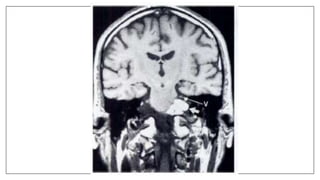

The two T1-weighted images of the head were obtained at exactly the

same location, yet the second image shows the VII cranial nerve while the

first does not.

The reason for the is explained by partial volume averaging.

The first slice was obtained with a thickness of 10 mm while the second was

at a thickness of 3 mm.

When a small structure is entirely contained within the slice thickness with

other tissue of differing signal intensity then the resulting signal displayed on

the image is a combination of these two intensities.

This may cause the small structure to disappear.